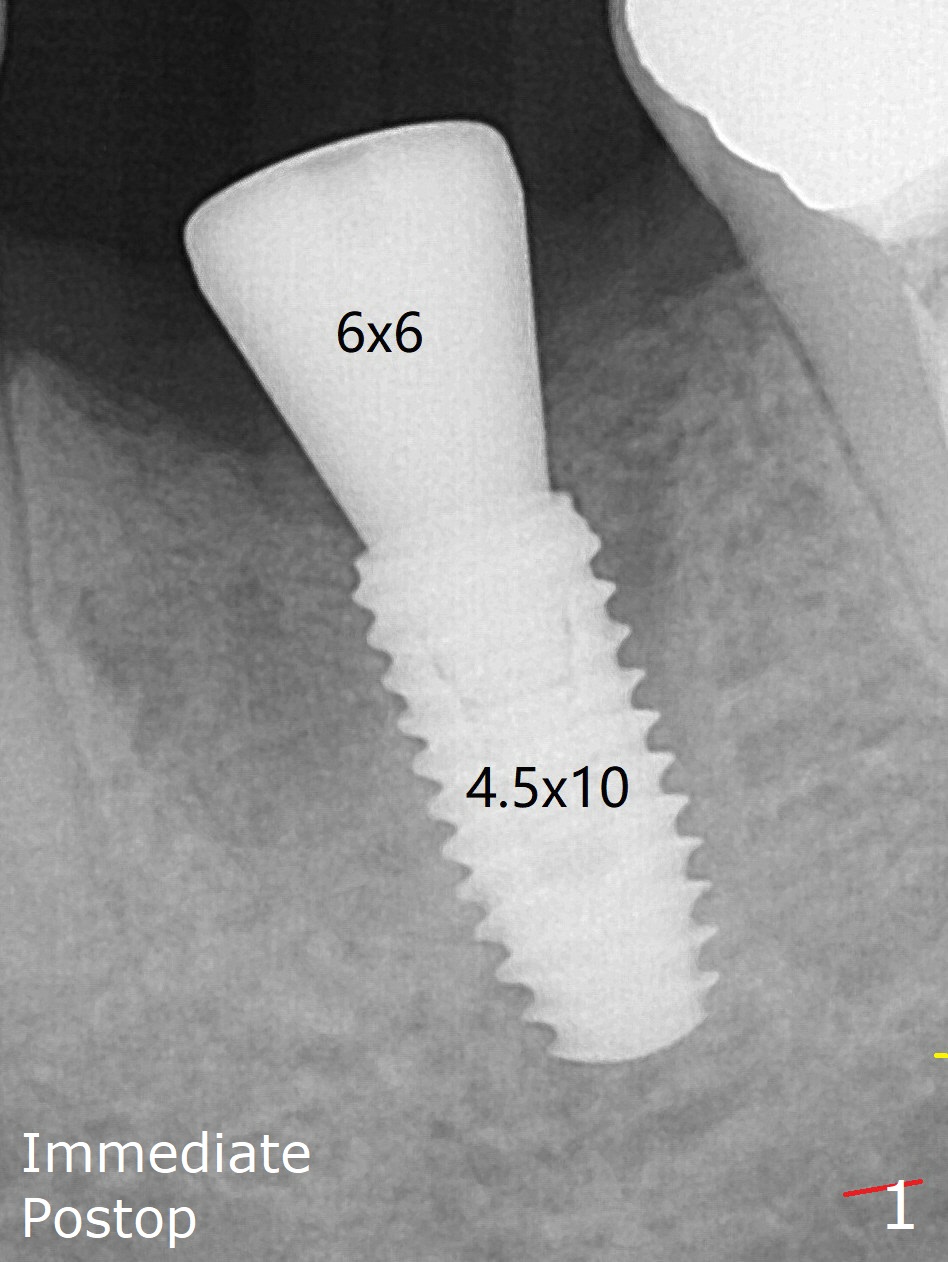

A long abutment is placed for restoration 4 months postop (Fig.3), increasing the chance of abutment screw loosening (as compared to immediate implant) if the abutment is incompletely seated.